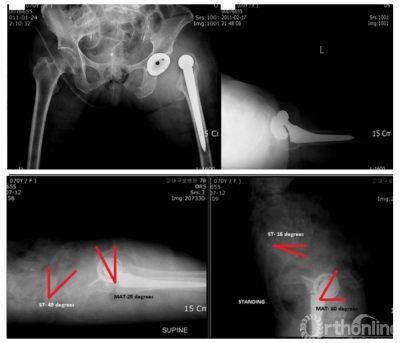

腰椎退变与融合对THA的影响

术前有腰椎融合史,同样会对THA术后关节稳定性产生影响。1项包含1456898例人工关节病例的荟萃分析显示,初始腰椎脊柱融合术增加THA的脱位和翻修风险。另1项配对分析也显示,融合节段越多,与假体相关并发症发生风险也越高。

图6 多例病例显示脊柱-骨盆固定后骨盆前倾,髋臼前倾角变小

脊柱-骨盆力线不良的患者髋臼假体过度前倾的患病率高,而且THA术后脊柱矢状面矫正导致髋臼前倾角减小,可能影响稳定性。脊柱融合术前倾的变化与骨盆盆倾斜的变化幅度甚至接近1:1。